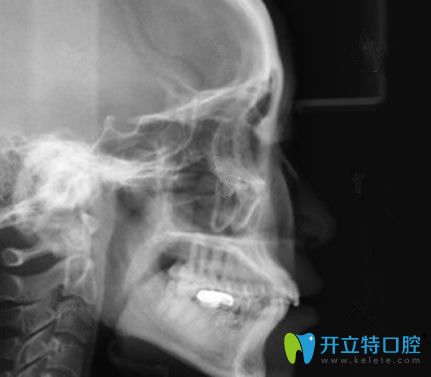

做手術(shù)前需要拍X光片,給大家看看我側(cè)面的片子吧:

平時(shí)只覺(jué)得嘴有些前突,但是從片中我看到,自己嘴突出的還不是一點(diǎn)兩點(diǎn),光看片子,似乎都能媲美遠(yuǎn)古人類(lèi),真是不忍直視。